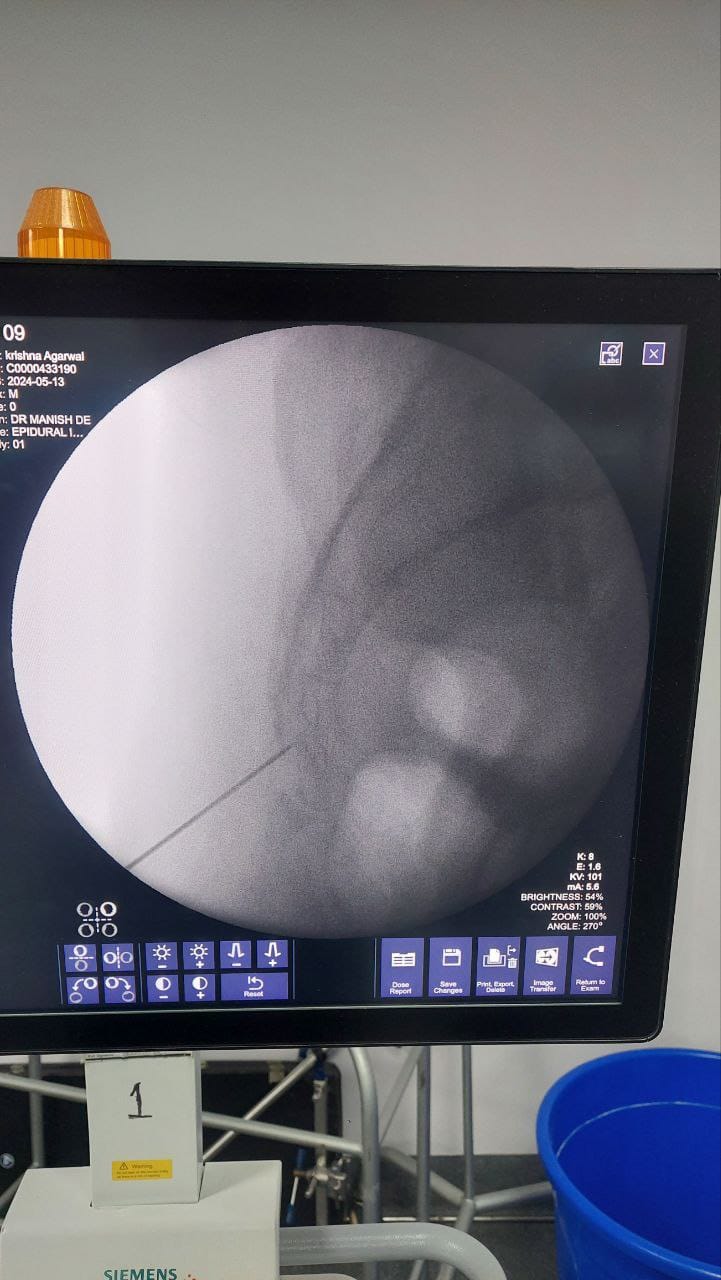

Procedures

Struggling with chronic pain? Get advanced, personalised pain management from Dr. Manish De, one of Kolkata’s leading pain specialists. From knee pain, heel pain, low back pain, frozen shoulder, migraines, cancer pain to post-TKR persistent pain—Dr. De offers safe, evidence-based treatments across multiple locations: